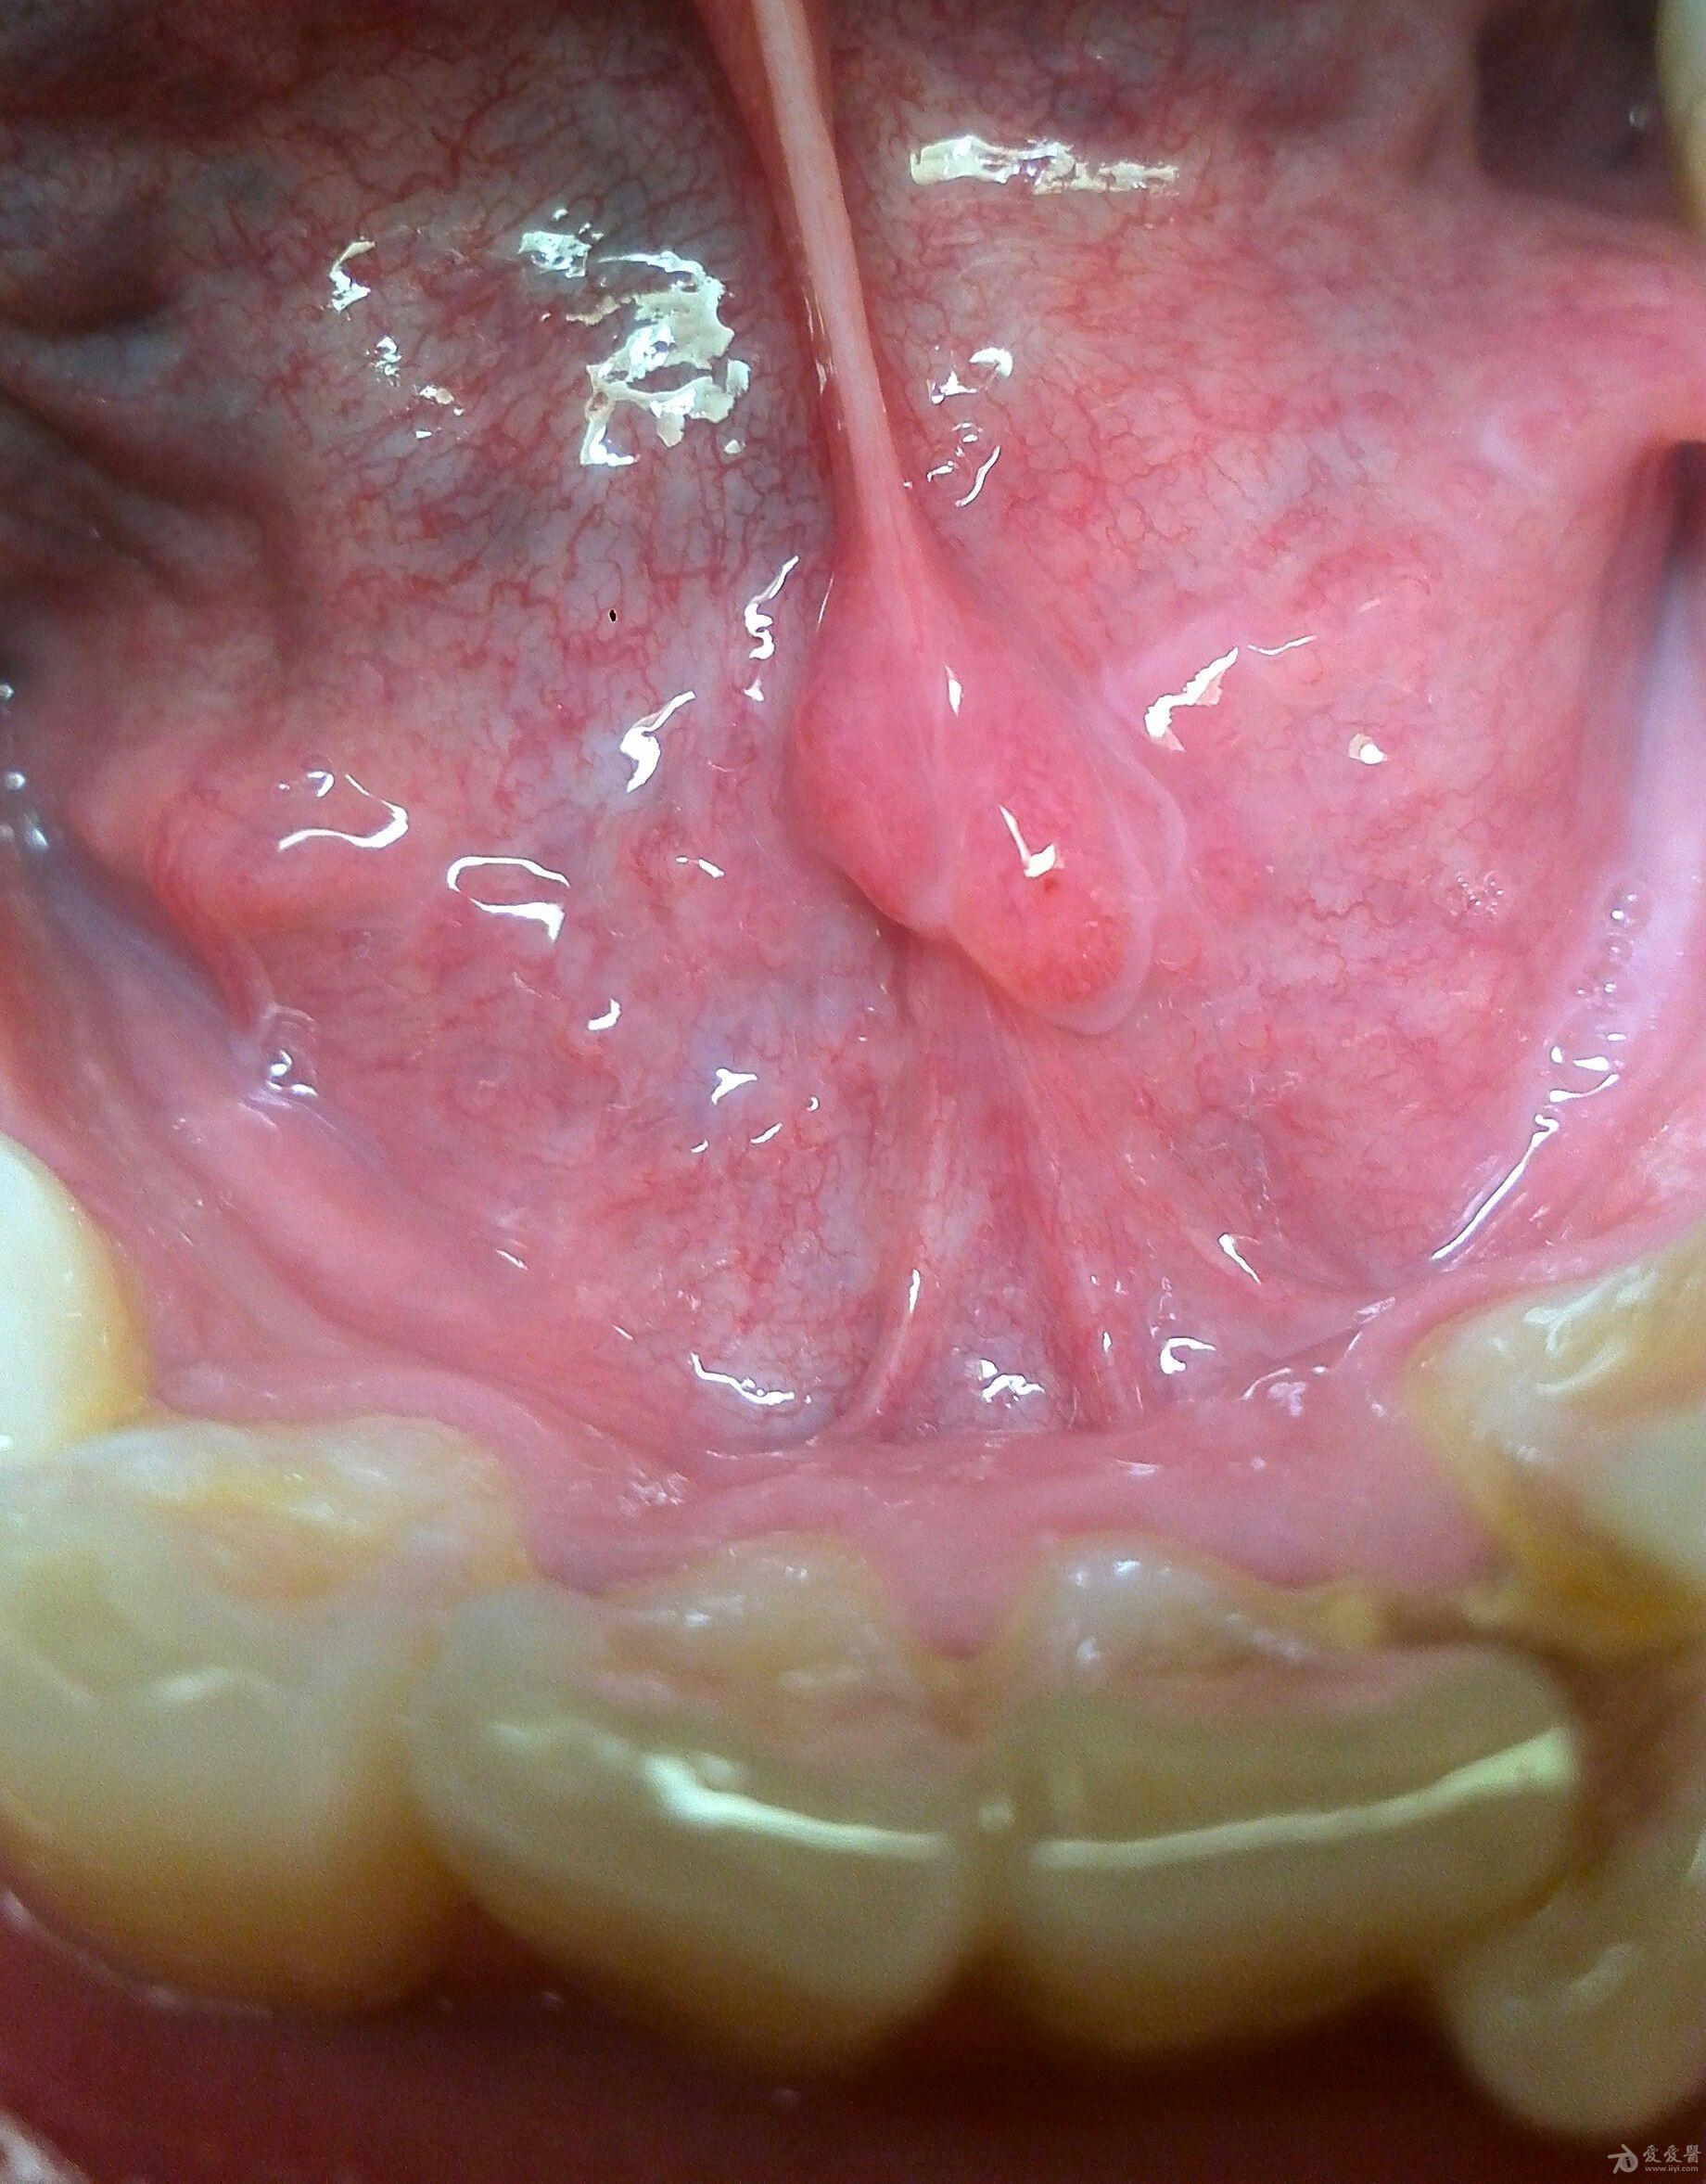

口腔正常组织还是囊肿?

口腔正常组织还是囊肿? 左面舌体上是什么?

第一幅图旁边的点装赘生物的是什么?